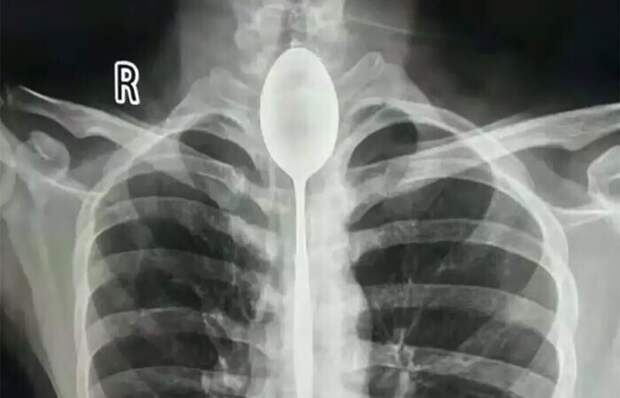

Китаец целый год проходил с ложкой в пищеводе. Удивительно, но ему это не доставляло неудобств